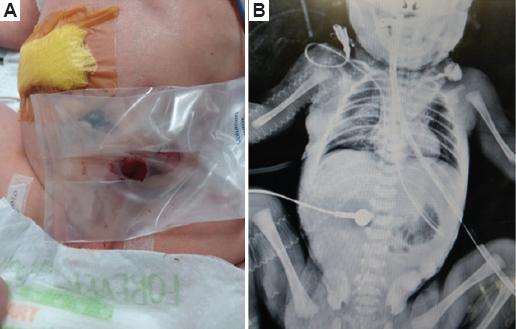

Se planea y realiza cirugía por un cirujano pediatra, corrigiendo la atresia esofágica mediante anastomosis de cabo proximal y distal por abordaje torácico posterior derecho, así como cierre de la fístula traqueoesofágica, dejando sello pleural. Se corrige la atresia intestinal, siendo esta duodenal de tipo 1, y se encuentra atresia rectal, por lo que se realiza una colostomía derivativa en el mismo acto quirúrgico, a los 4 días de vida extrauterina (Fig. 5).

Es intubada antes de iniciar la cirugía y se mantiene así en la unidad de cuidados intensivos neonatales para evitar la dehiscencia de la anastomosis. Se da por terminada la cirugía sin complicaciones ni incidentes, y se realiza una radiografía de control a las 12 horas (Fig. 5).